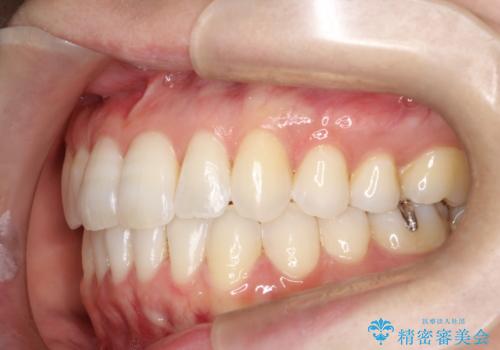

【インビザライン】前歯の凸凹をなおしたい

- 前歯の凸凹を主訴に来院されました。

上顎の急速拡大を行なったのちインビザラインにて治療を行なっております。

今回のケースは後戻りのリスクを低くし、またディスキング量を減らすために上顎の急速拡大を行なっております。